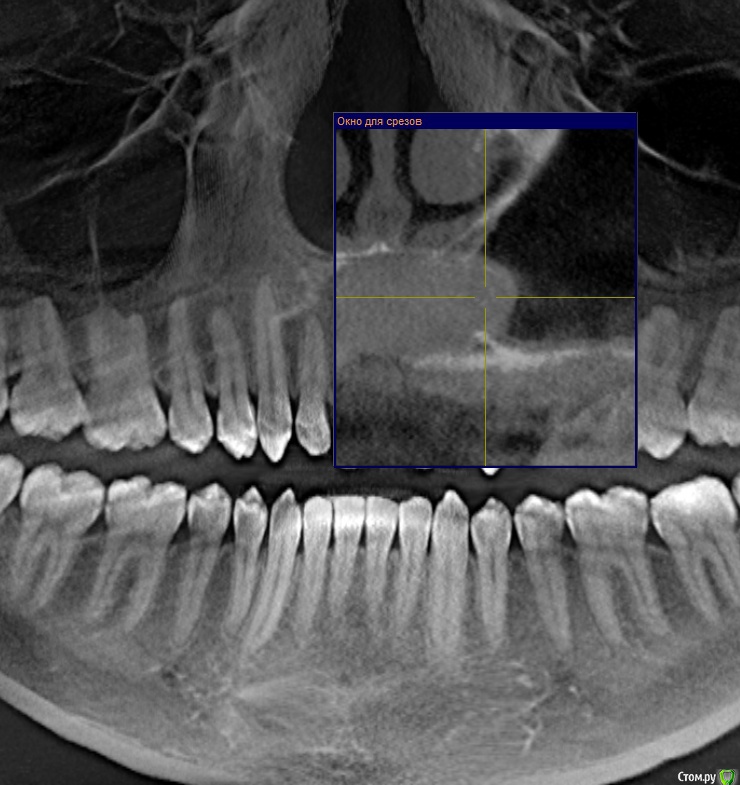

mike302459 Опубликовано 13 июня, 2018 Поделиться Опубликовано 13 июня, 2018 (изменено) Описание:Где-то полгода назад у зуба появилась сильная чувствительность, на еду, воду, не важно какой температуры. Это прошло за пару недельВ марте я нащупал языком некую припухлость, "шишка" на десне над передними зубами. С течением времени она заметно не изменялась.Примерно 20ого мая, начала воспаляться и пухнуть. Немного опухла губа, десны, и край десны "налез" до середины зуба.Далее где-то через неделю образовался свищ, над зубом 2.1, и начала вытекать белая субстанция, и янтарная жидкость из свища и между зубом и десной.Еще пару дней оттуда текло, потом всё зажило, отёк спал, шишка на десне осталась как в начале, в марте.Цвет одного зуба изменен - 2.1(уже давно).Всё это время каких то сильных болей не было, температуры не было. Потом пошёл в поликлинику, сделали КТ, не стали лечить, посоветовали врача, тот врач посоветовал еще врача.В последнем месте на словах предложили примерно такой план лечения. (С трудом это всё выяснил, диалог не задался, да и были неприятные моменты)" Сейчас сделаем разрез, промоем полость кисты, потом пойдешь в свою поликлинику пусть там запломбируют канал. Будешь промывать самостоятельно эту полость несколько месяцев, она будет зарастать. Но скорее всего всё не зарастёт, придешь на еще одну операцию" (Какую?)На бумаге потом написали так: Диагноз: Радикулярная киста зуба 2.1. Пациенту рекомендовано хирургическое лечение в объеме резекции корня зуба 2.1 + цистотомия.1. Эндодонтическое лечение зуба 2.1. Вопросы:1. Чтобы вы посоветовали по данной проблеме?И если возможно, то посоветуйте где в Москве можно этим заняться.2. И что сначала делать: резать кисту или пломбировать канал. Я читал мнения, что сначала запломбировать канал, как причину. Но вот откроют его, а оттуда же польётся содержимое кисты? прикрепляю скриншоты из программы со снимком. На втором немного изменил плоскость. Изменено 13 июня, 2018 пользователем mike302459 Ссылка на комментарий